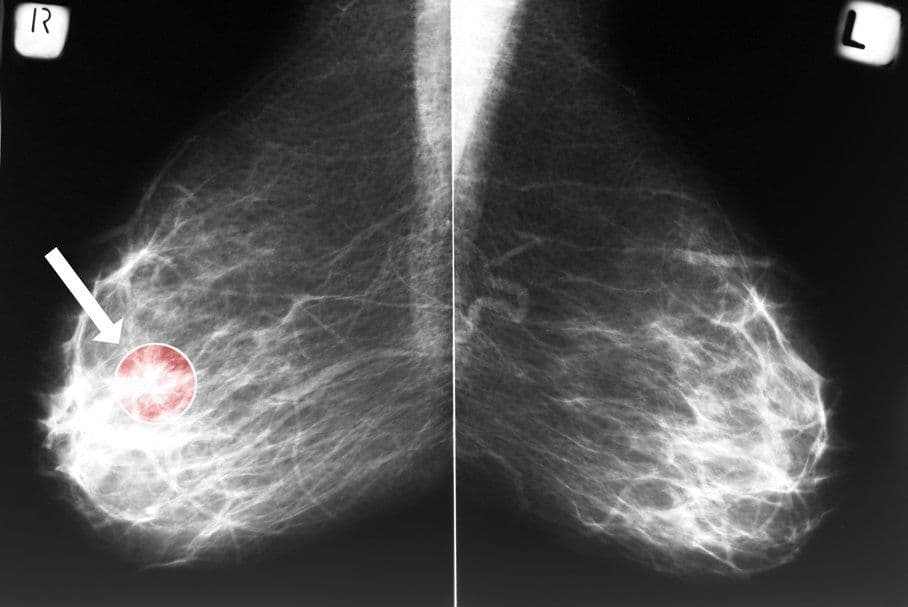

Poniżej zdjęcie raka piersi, widoczne na mammografii.

Skuteczną metodą badań przesiewowych jest mammografa sutka (badanie radiologiczne polegające na wykonaniu zdjęć obu piersi osobno, w dwóch projekcjach). Ponadto stosuje się USG piersi, które jest przeznaczone dla kobiet posiadających „gęstą” strukturę sutka. Warto zaznaczyć, że jest ono tylko uzupełnieniem diagnostyki, której podstawą powinno pozostać badanie mammograficzne.